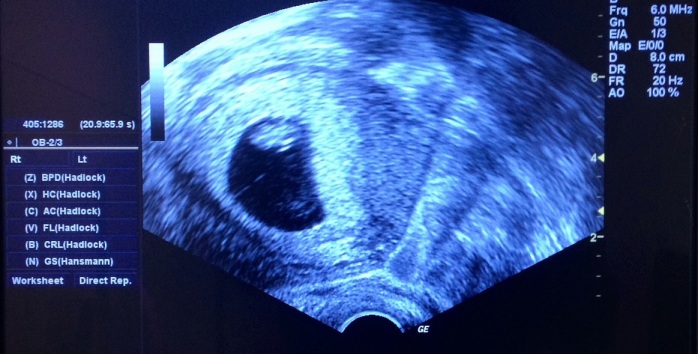

Pero luego de varios exámenes, que incluyeron una ecografía abdominal y una tomografía computarizada, el doctor Sirshendu Giri, determinó que se trataba de un embrión muerto alejado en el abdomen del menor., de acuerdo a lo que consignó el portal de noticias local India Times.